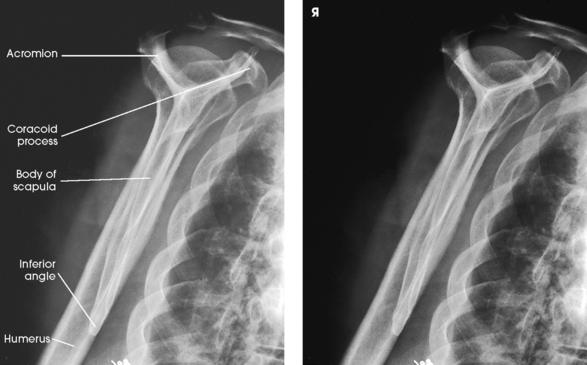

Structures shown: The image shows the bony and soft structures of the shoulder and proximal humerus in the anatomic position (Figs. 5-14 to 5-16). The scapulohumeral joint relationship is seen.

External rotation: The greater tubercle of the humerus and the site of insertion of the supraspinatus tendon are visualized (see Fig. 5-14, A).

Neutral rotation: The posterior part of the supraspinatus insertion, which sometimes profiles small calcific deposits not otherwise visualized (see Fig. 5-14, B), is seen.

Internal rotation: The proximal humerus is seen in a true lateral position. When the arm can be abducted enough to clear the lesser tubercle of the head of the scapula, a profile image of the site of the insertion of the subscapular tendon is seen (see Fig. 5-15).